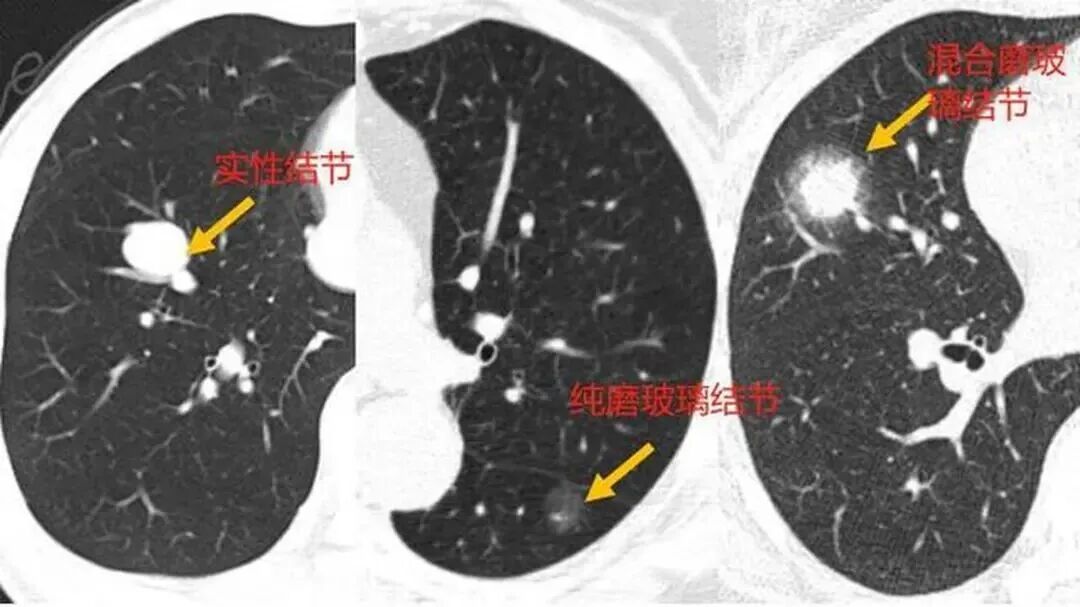

首先,是影像学手段的进步。十年前,大部分人没有接受过高分辨率的彩超或低剂量CT,如今几乎成了体检标配。结节往往在毫米级就能被发现,自然检出率节节攀升。

以甲状腺结节为例,中国医学科学院肿瘤医院2021年一项多中心研究表明:超过85%的甲状腺结节为良性,恶性比例不足15%。乳腺结节中也有类似结论,大部分是纤维瘤或囊肿。肺结节虽然更敏感,但直径<8毫米的孤立性肺结节,其恶性概率不足5%。

肺部:直径<6mm的结节,多数观察即可,通常每6-12个月复查一次CT。